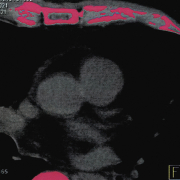

Some chest pain, a pounding heart, dizziness and shortness of breath saw Jeff headed to his doctor to get some answers. His doctor sent him off for a scan to see everything that was going on inside Jeff’s heart.